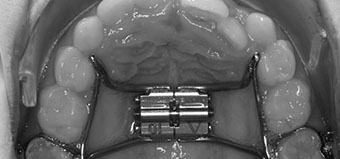

Removable appliances

Removable appliances have wire springs which are attached to a smooth, plastic plate. It’s held securely in the mouth by wire clasps and encourages simple tooth movements. They are usually used instead of braces for young children who still have some baby teeth.